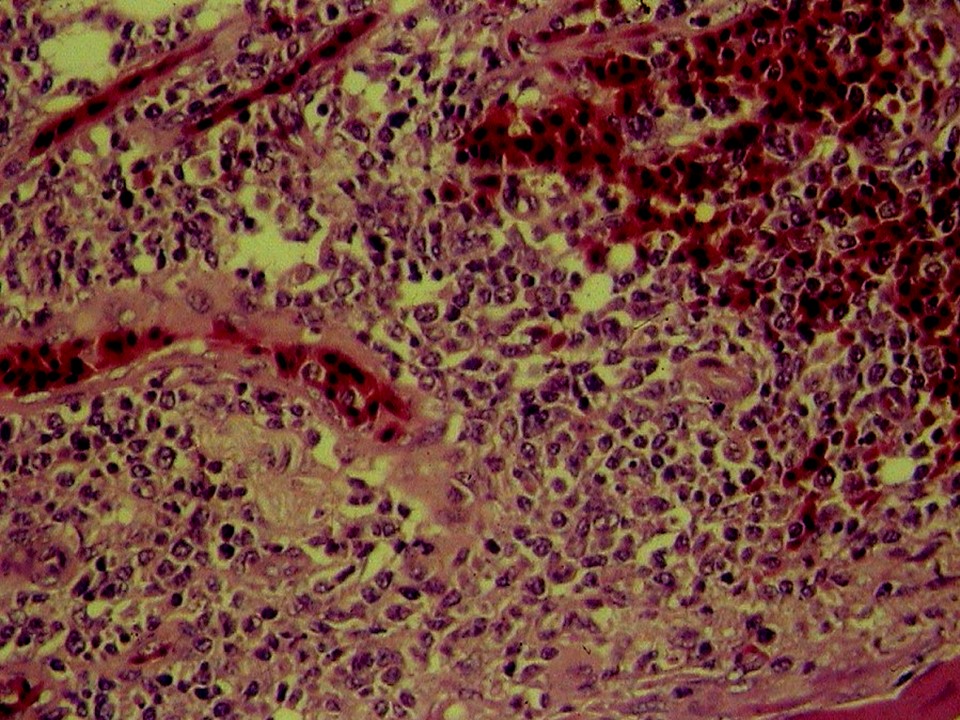

疾病中文名稱:馬立克病

疾病英文名稱:Marek's disease

作者:蔡信雄教授